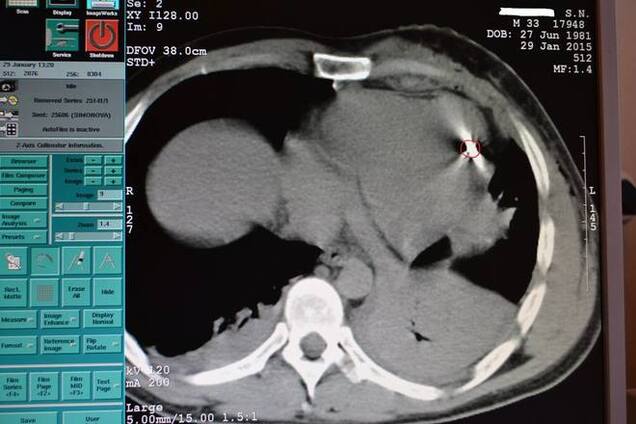

Торакоабдоминальное ранение, резекция легкого, осколок в стенке сердца.

Еще бы 1-2 милиметра – и не помог бы никто.